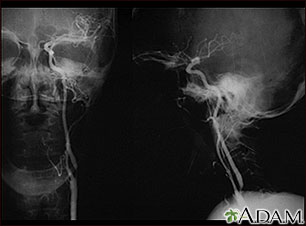

Carotid stenosis, x-ray of the left artery

A carotid arteriogram is an x-ray study designed to determine if there is narrowing or other abnormality in the carotid artery, a main artery to the brain. This is an angiogram of the left common carotid artery (both front-to-back and side views) showing a severe narrowing (stenosis) of the internal carotid artery just beyond the division of the common carotid artery into the internal and external branches.